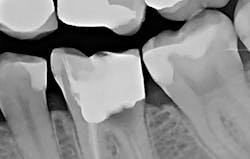

The patient was anesthetized with 1.7 ml of 4% articaine with epinephrine 1:100,000. The entire procedure was performed using the "Hard and Soft Tissue" setting. The gingiva was flapped to expose bone using the 0.25 mm spot size with 1% mist and cutting speed between 20% and 50% (figures 9-10). Only 0.5 mm of tooth structure was coronal to the alveolar bone. The osseous tissue was removed to establish biologic width and expose tooth structure coronal to bone for a proper restoration (figure 11). Proper positive bony architecture was maintained. The 0.75 mm spot size was used with 100% mist and cutting speed between 30% and 60%. A temporary restoration was placed, followed by one suture (figure 12). The total procedure time was 50 minutes. The patient was reevaluated after seven days (figure 13), and the final crown was placed (figure 14).

With traditional instruments, this procedure is typically completed with a scalpel and high-speed handpiece with burs. A larger flap is required to improve visibility and instrumentation. However, with Solea's precision and small spot-size options, a much smaller flap was needed. There was less bleeding, resulting in a cleaner surgical site and faster postoperative healing. As the radiograph and photos show, excellent conditions for the final restoration were established. The final crown demonstrated sound margins and evidence of proper biologic width. As the five-day follow-up photo shows, the healing time was fast, and tissues appear healthy.

Figure 11: Flapped, postosseous reduction